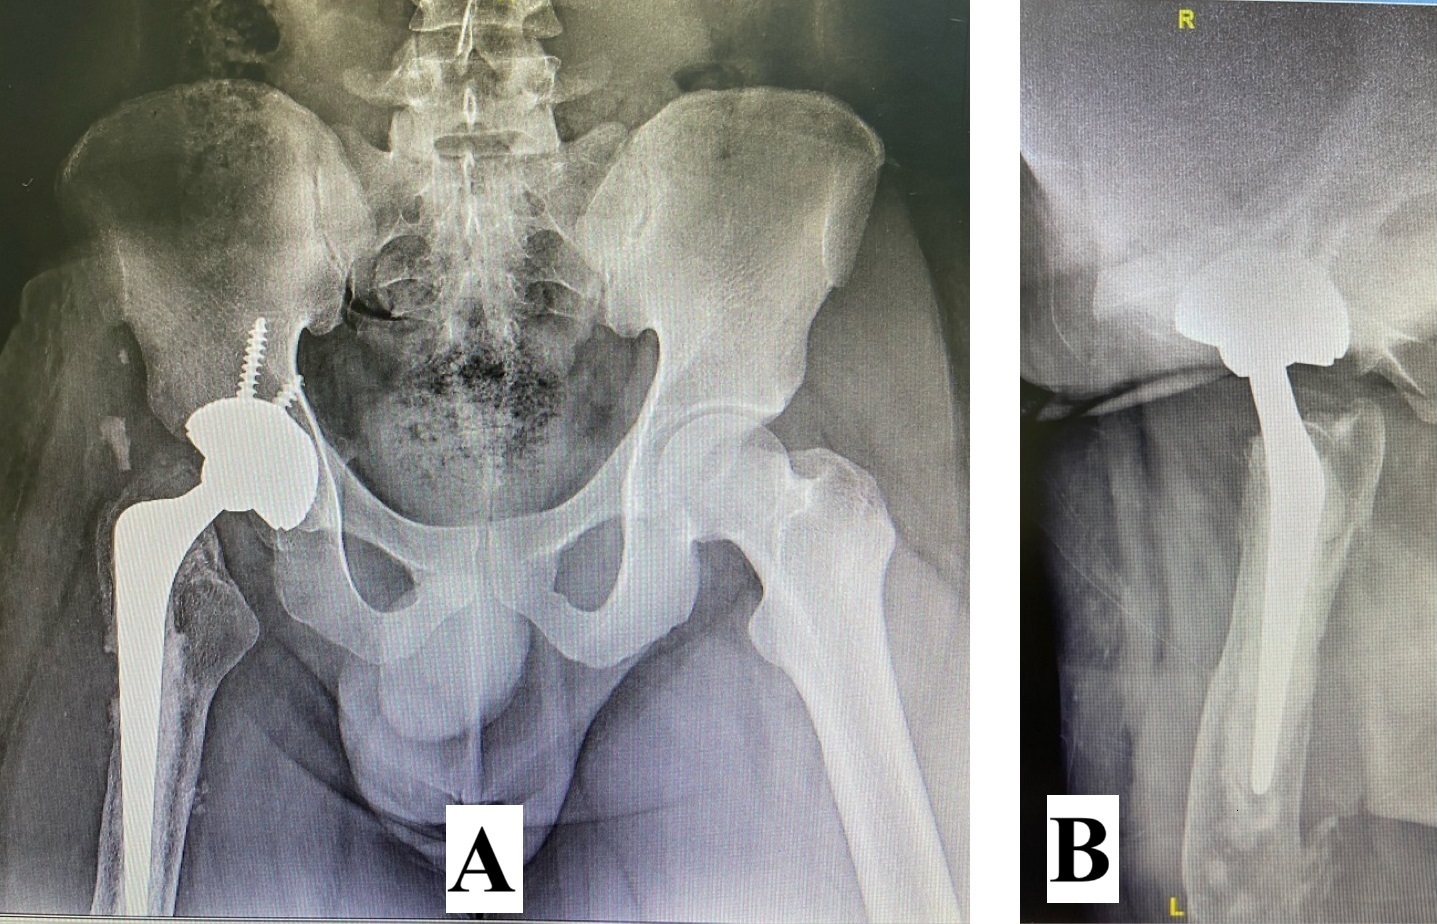

Initial management involved screw fixation of the femoral neck, wound debridement of the right thigh, and placement of an external fixator across the right knee (Figures 4 and 5), followed by a one-week course of intravenous cefuroxime. By January 2021, the right leg had become gangrenous and deemed nonviable. Right above-knee amputation (AKA) with adductor myodesis was performed, followed by intravenous cefuroxime for another week.

The first-stage revision surgery was performed in December 2021. Preoperative radiographs (Figure 6) revealed an AVN of the right femoral head, nonunion of the femoral neck, and osteopenia of the proximal femur. Surgical procedures included debridement of the AKA stump and removal of the native femoral head, followed by the insertion of an antibiotic-loaded cement spacer. Postoperative cultures again identified Enterobacter cloacae, necessitating a six-week course of intravenous Meropenem. A postoperative radiograph (Figure 7) showed the placement of an articulated antibiotic-loaded cement spacer. By February 2022, after a two-week antibiotic-free period, the patient’s CRP level had decreased to 18.2 mg/L. Hip aspiration performed in June 2022 showed a further decrease in CRP to 10.2 mg/L, with negative cultures.